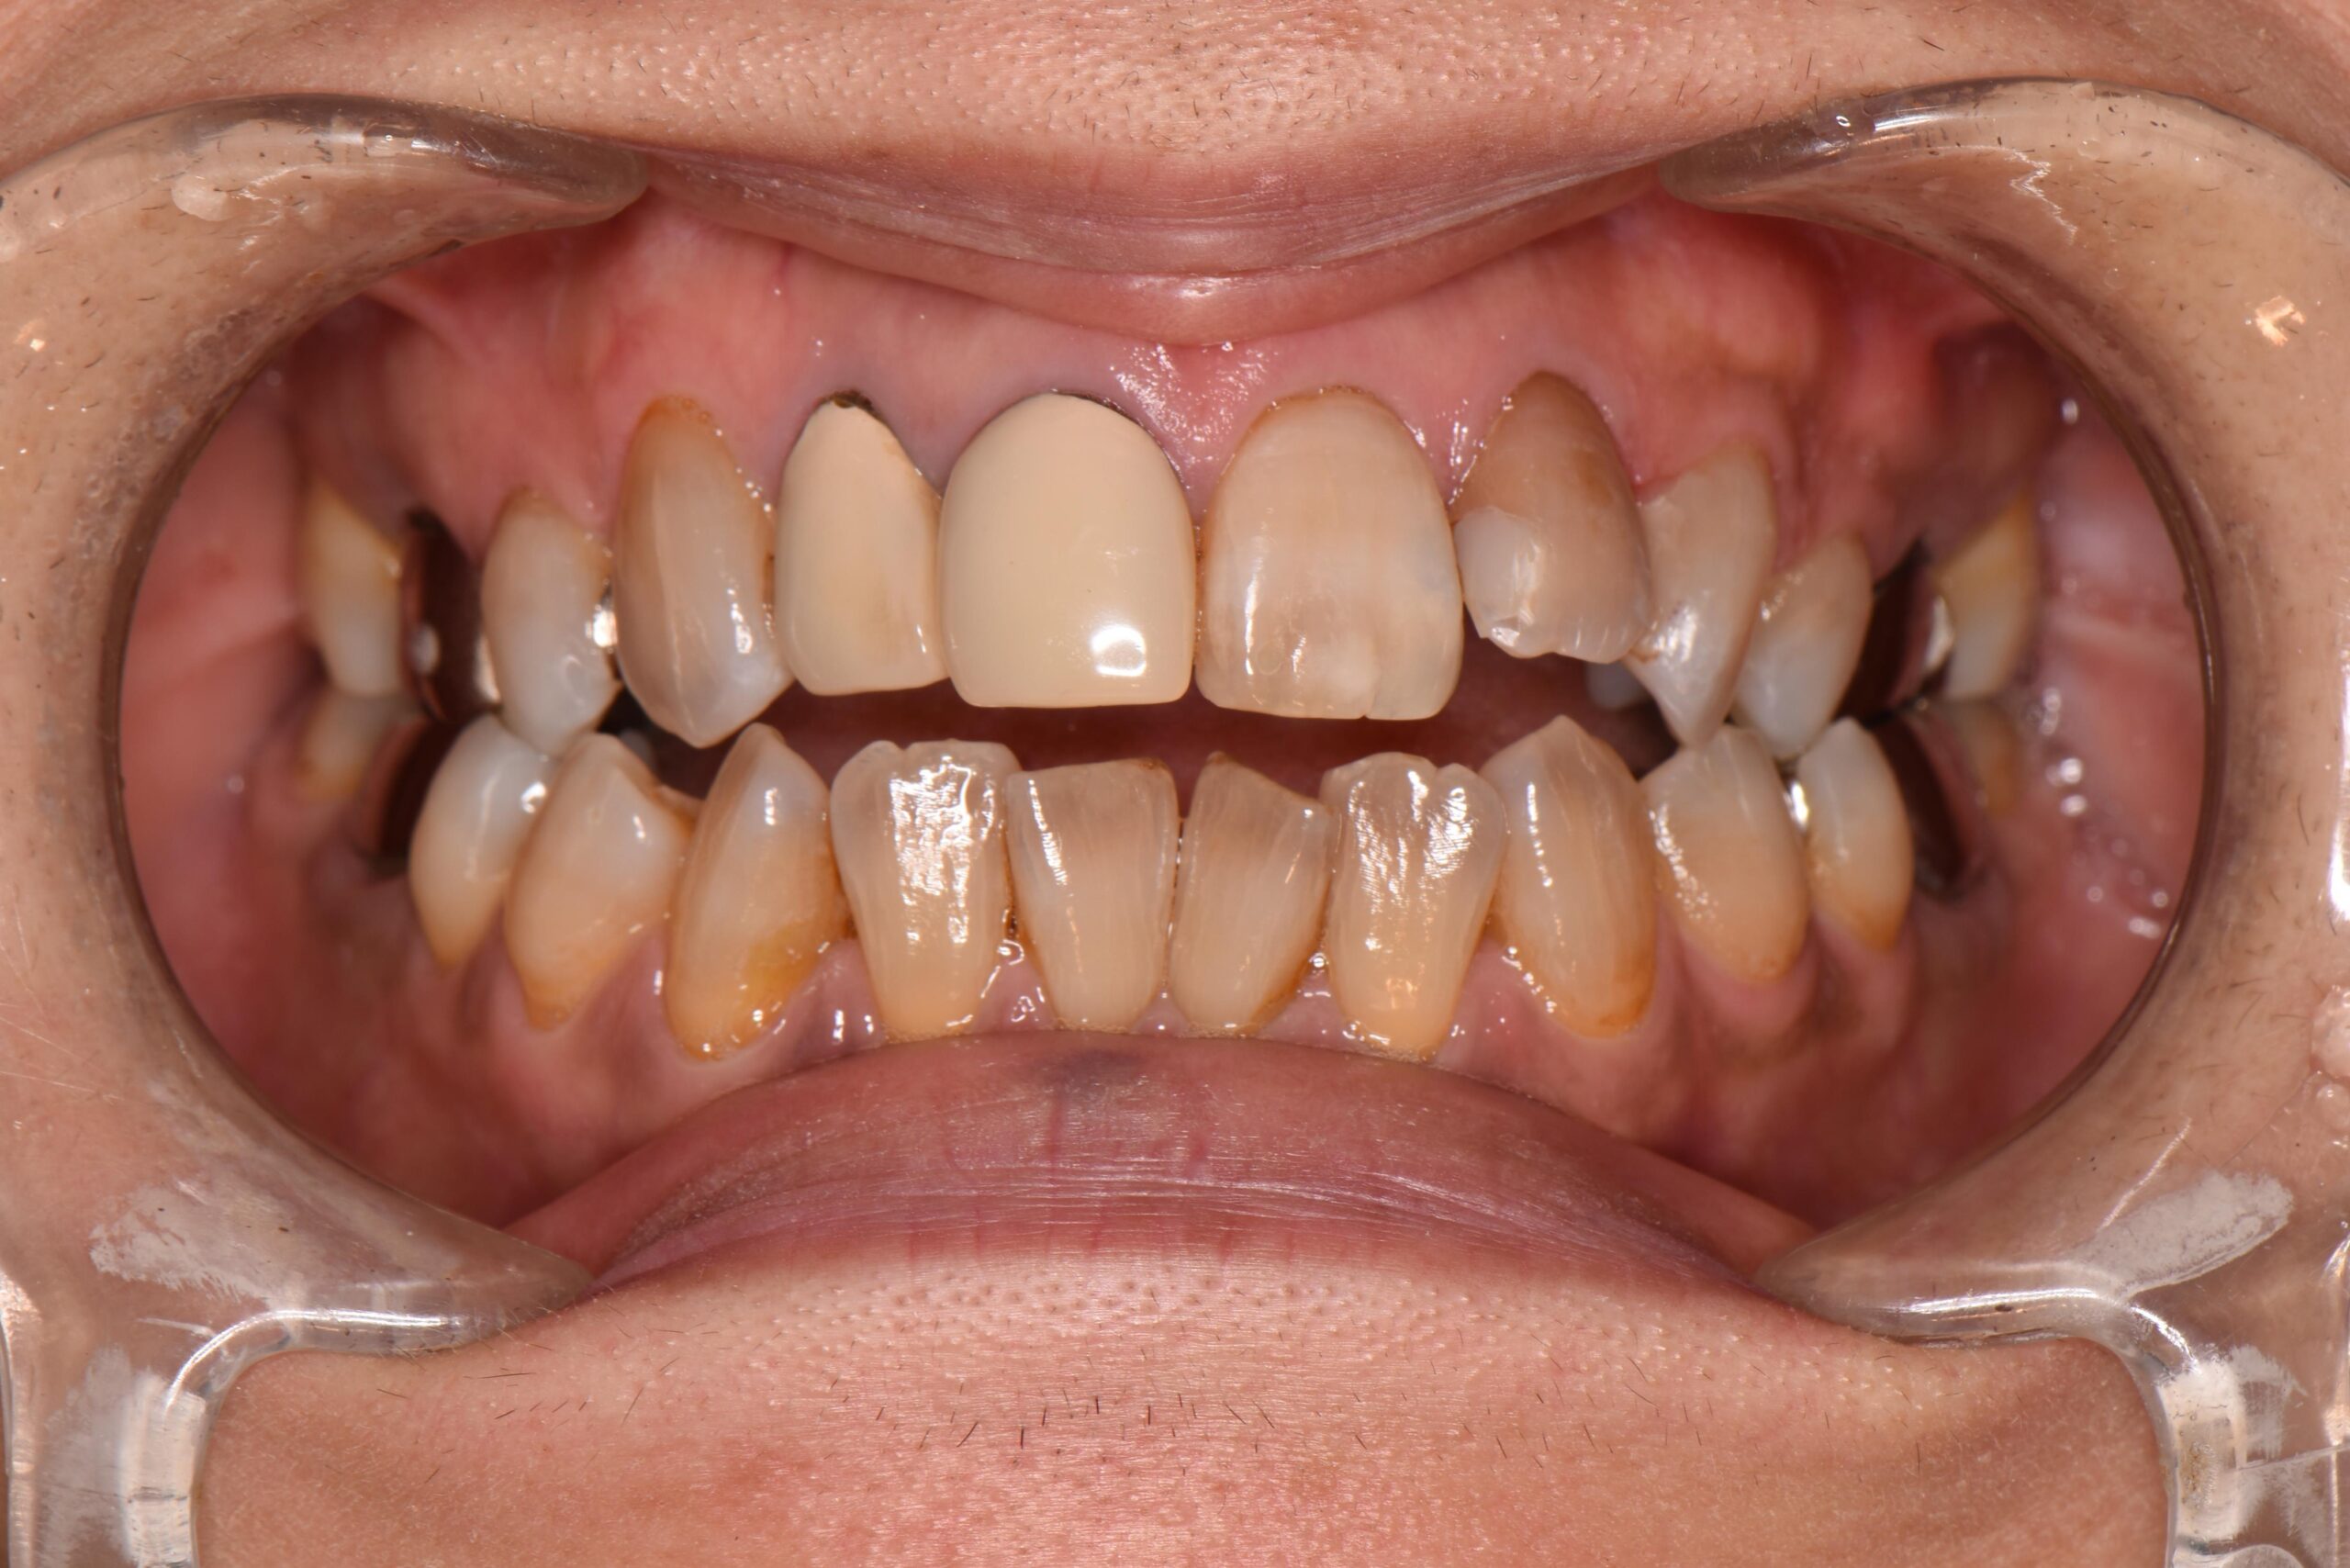

下の歯が上の歯よりも前に出ている状態です。

顎関節への負担や全身のバランスが悪くなる場合があり、お子様の場合は咀嚼が不十分になることで体の発育にも影響する可能性もあります。

よく噛むことは食べ物の消化のしやすさにも直結し、全身の健康にも影響します。

矯正治療で噛み合わせを整えることは、食事のしやすさの改善にも繋がります。